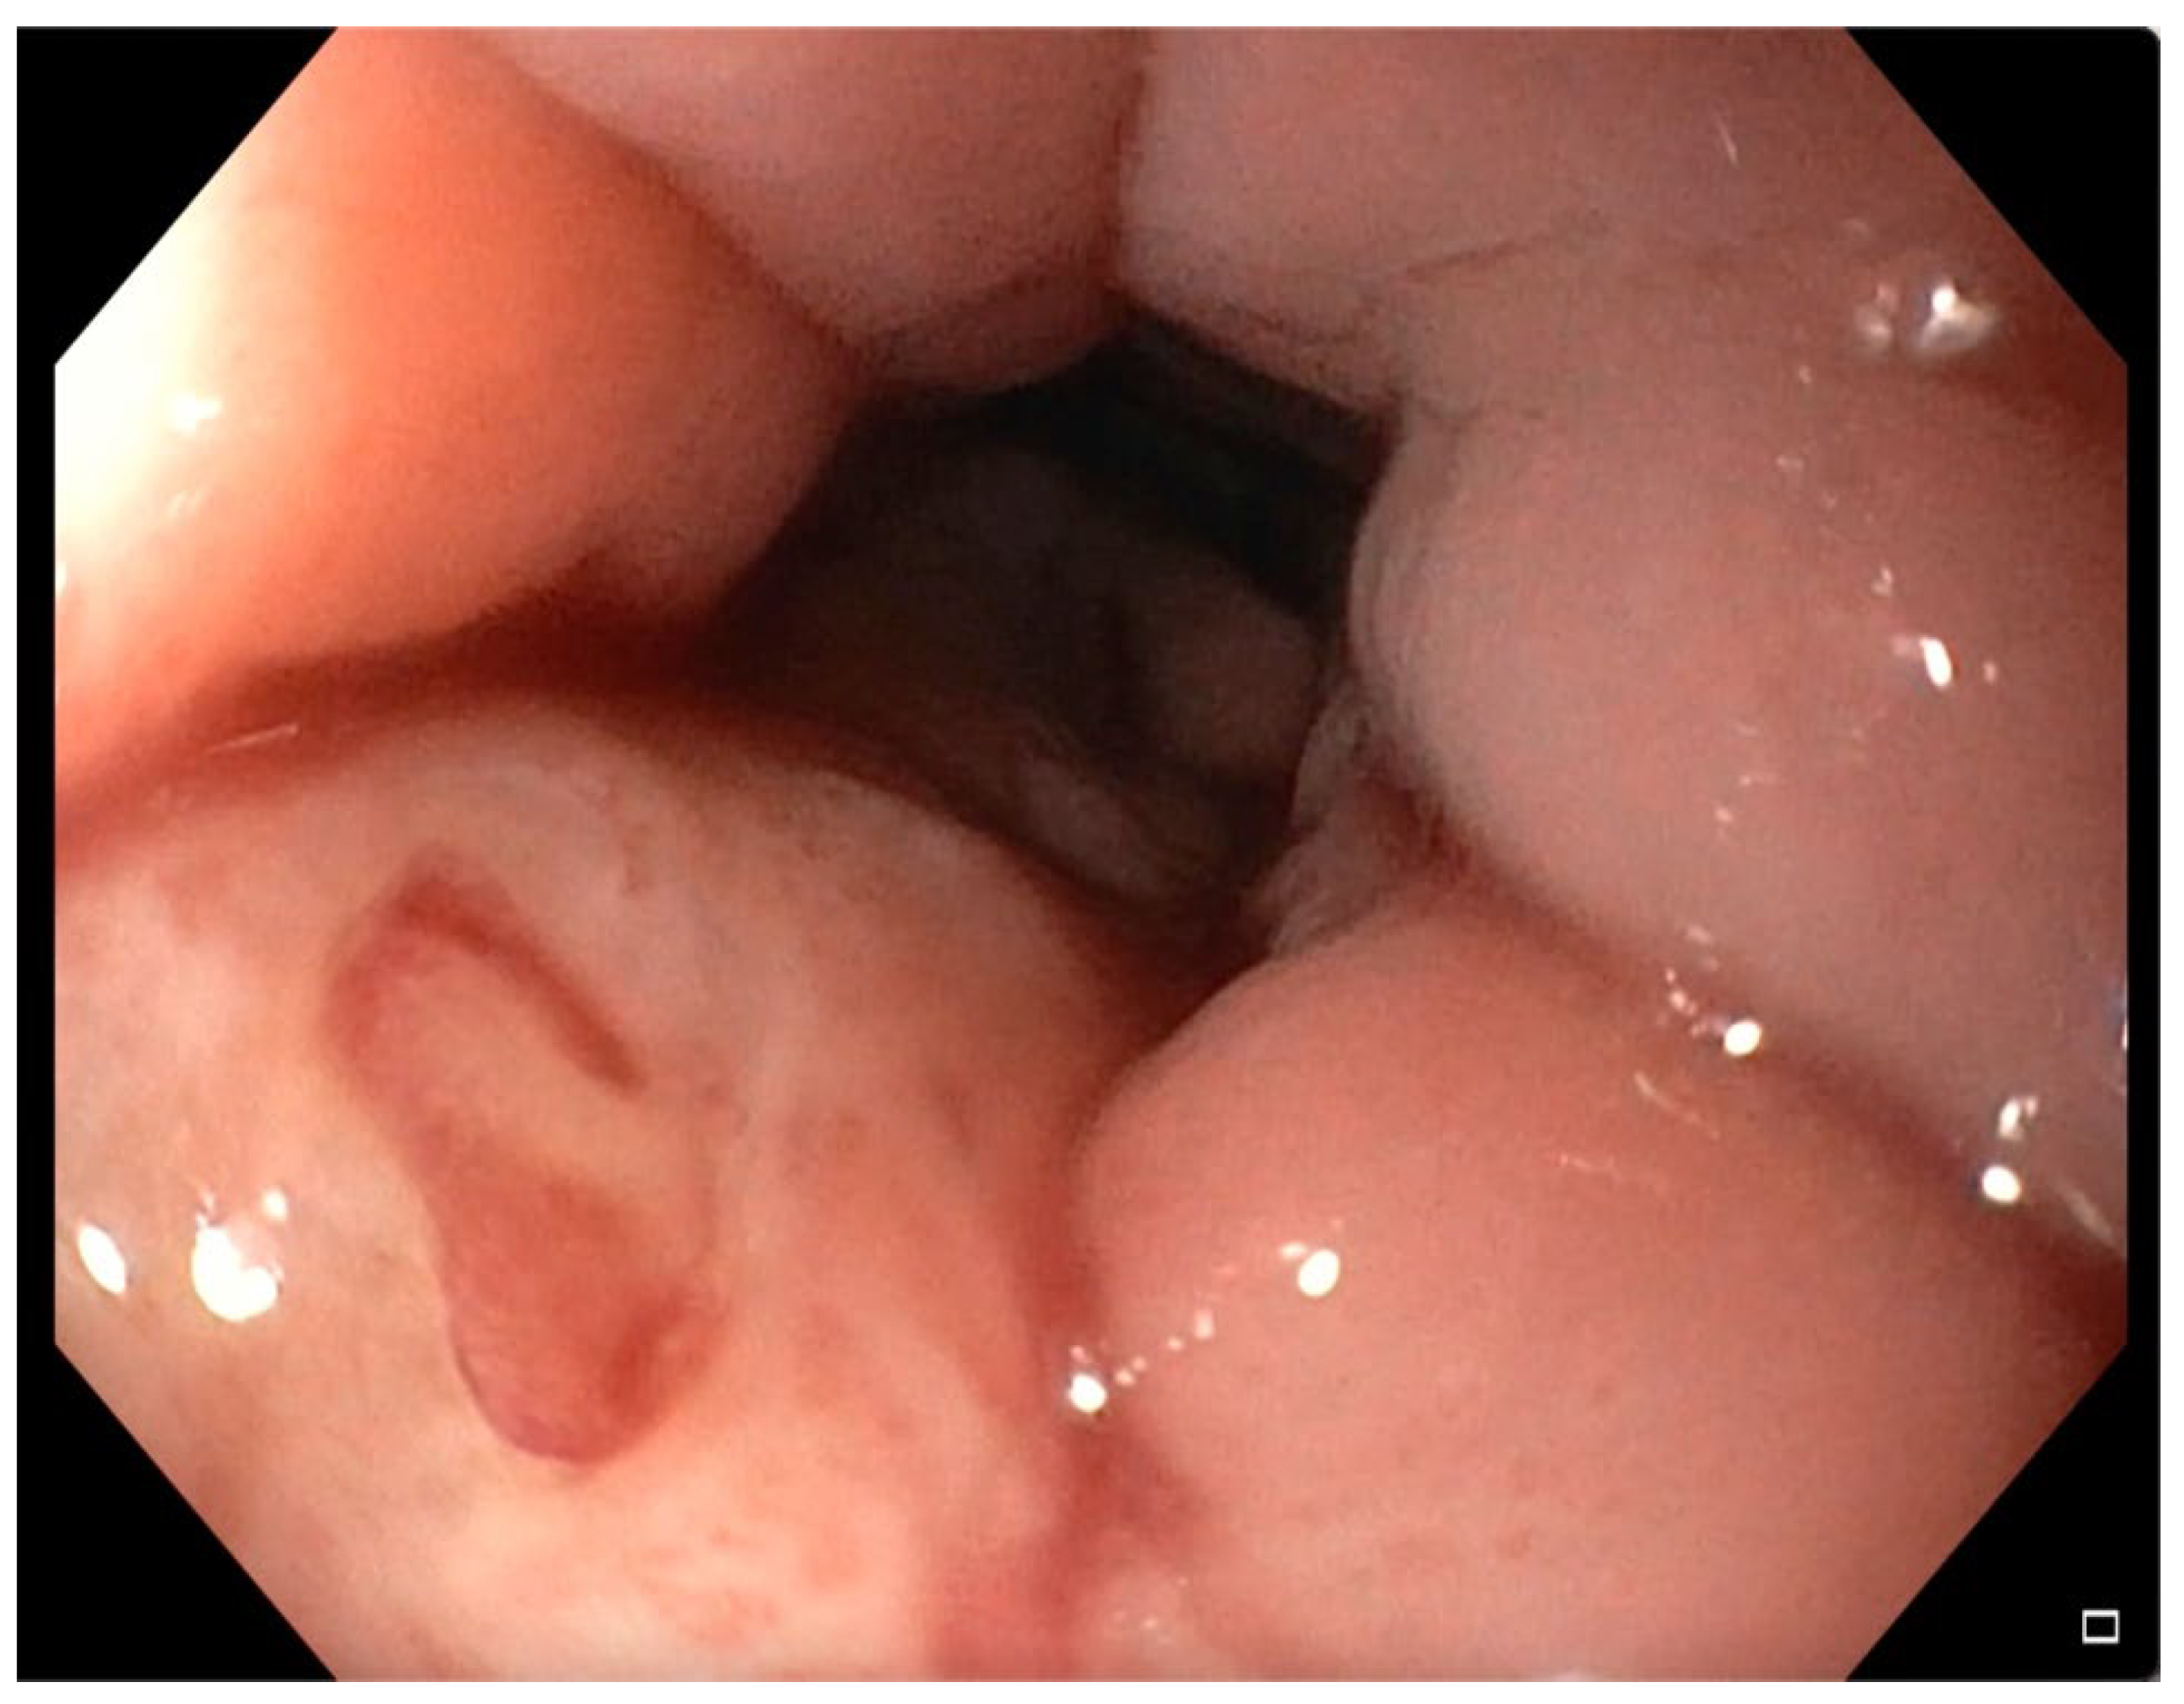

2.1. Case 1

2.2. Case 2